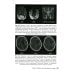

Аннотация: Инсульт и цереброваскулярная патология у детей и подростков: руководство для врачей

В книге описаны современное состояние проблемы инсульта и цереброваскулярных заболеваний у детей и подростков, накопленный опыт диагностики и подходов к терапии данной патологии в различных клиниках. Особое внимание уделено этиологическим факторам, приводящим к поражению сосудов головного мозга в педиатрии, что определяет подходы к терапии в острейшем периоде, а также оценке рисков рецидива и вторичной профилактике. Представленный опыт первого в России центра по лечению цереброваскулярной патологии у детей позволяет оценить распространенность детского инсульта в России, стандартизировать подходы к диагностике и лечению инсультов у детей с последующей оценкой наиболее эффективных методов терапии. Накопленные данные показывают, что более результативным является не мультидисциплинарный подход при ведении пациентов с цереброваскулярной патологией, а создание команды специалистов, подготовленных к решению данной проблемы. Издание предназначено врачам различных педиатрических специальностей, студентам старших курсов медицинских вузов.

Инсульт и цереброваскулярная патология у детей и подростков: руководство для врачей